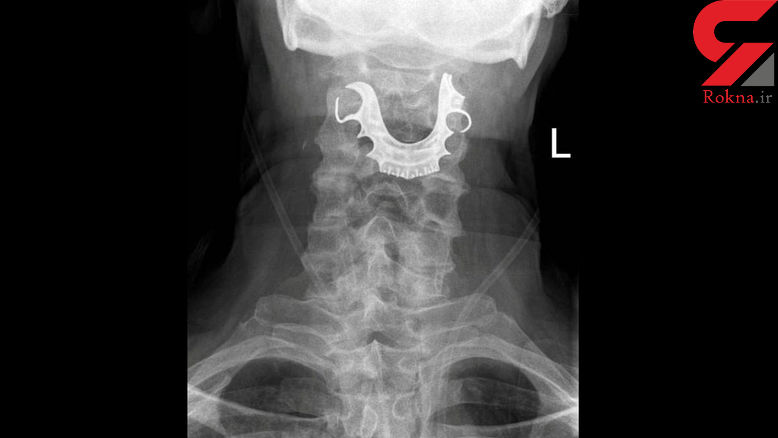

گیر افتادن دندان مصنوعی در گلو پیر مرد او را راهی بیمارستان کرد.

از قرار معلوم هنگام جراحی دندان مصنوعی بیمار داخل دهانش بود که بی توجهی پزشکان و پرستاران موجب شد تا دندان داخل گلویش گیر کند و راه تنفسی او را ببندد.

بیمار ۷۲ ساله مدعی بود که پس از به هوش آمدن در بیمارستان پزشکان به او گفتند که دندانش گم شده و او تا زمان مرخص شدن بدون دندان مانده بود تا این که چندی پیش متوجه گلو درد و خونریزی شدید و بسته شدن راه تنفسی اش شد که با مراجعه به بیمارستان راز بی احتیاطی پزشکان فاش شد.